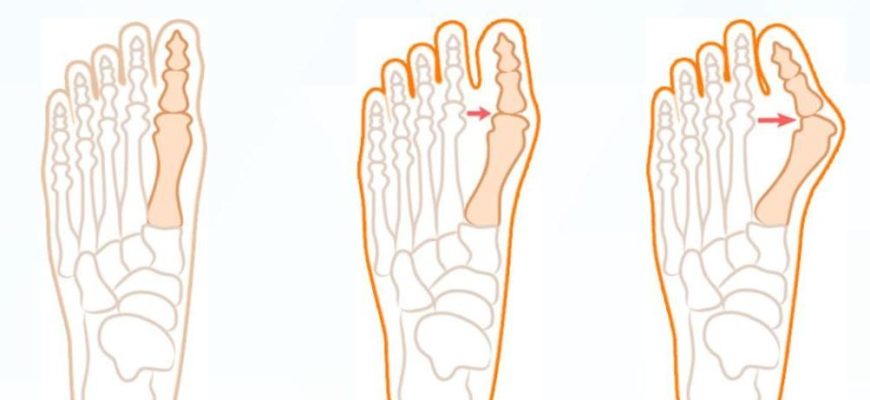

Изменения стопы при деформации: понимание‚ профилактика и лечение Современные люди ежедневно подвергаются огромным нагрузкам на стопы‚

Изменения стопы при деформации: как сохранить здоровье и функцию обуви Когда речь заходит о здоровье нашего организма, стопы зачастую остаются в тени

Изменения стопы при деформации: как распознать и предотвратить последствия Стопа — это уникальный механизм, подвергающийся большим нагрузкам каждый день.